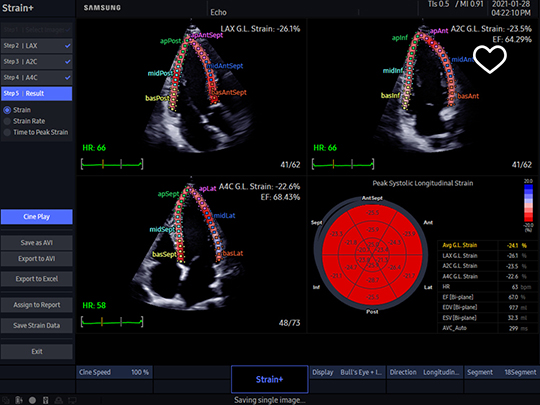

PN2-4

- Application: abdomen, cardiac, vascular, pediatric, TCD